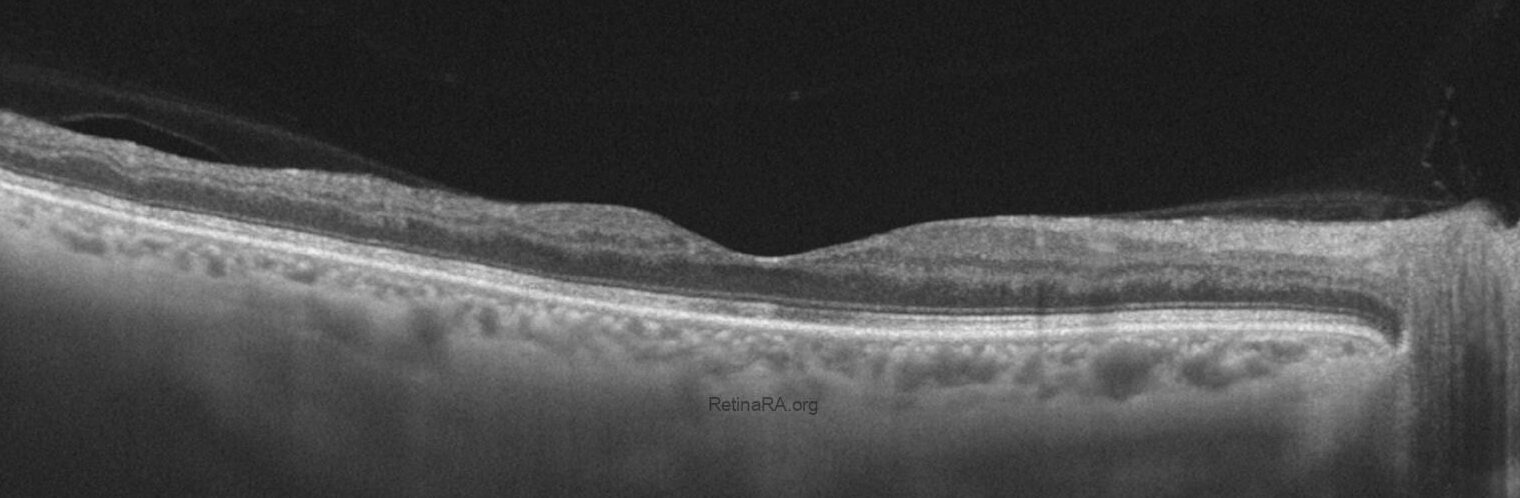

The optical coherence tomography (OCT) image shows significant macular edema with marked retinal thickening. Multiple intraretinal hyporeflective cystoid spaces are present, consistent with cystoid macular edema. There is also a dome-shaped elevation at the fovea, suggesting serous detachment of the neurosensory retina. The normal foveal contour is lost, and the retinal architecture appears markedly disorganized. Hyperreflective foci are scattered within the retina, likely representing hemorrhagic or exudative material. These findings are characteristic of macular involvement in central retinal vein occlusion.

The post-treatment OCT image demonstrates a marked reduction in macular edema with restoration of the foveal contour and resolution of intraretinal cystoid spaces. The outer retinal layers appear more distinct, and overall retinal thickness has normalized compared to baseline. Notably, there is thinning in the temporal macular region, likely reflecting atrophic changes secondary to chronic ischemia and prior edema. These findings indicate a favorable anatomical response to anti-VEGF therapy, while also highlighting residual structural damage in the temporal retina.